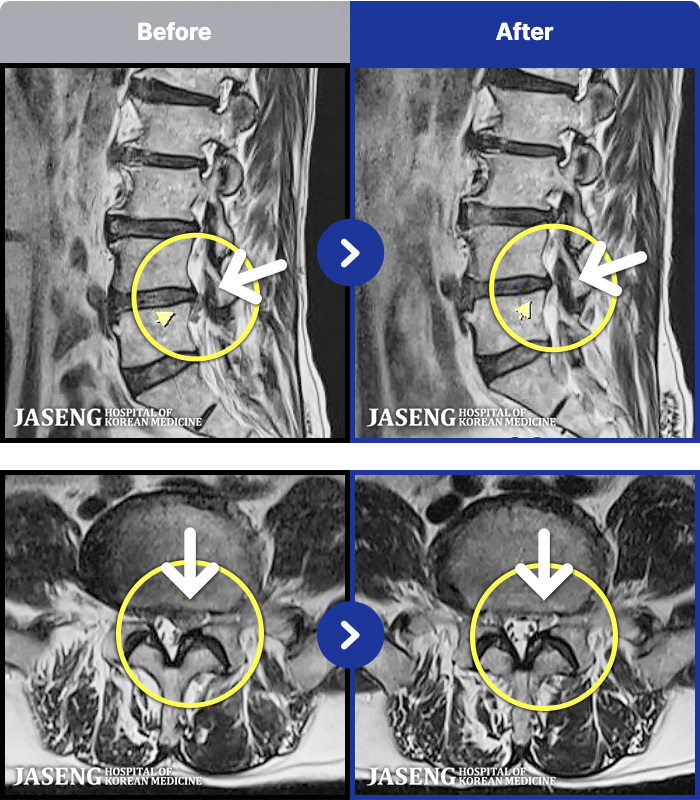

- MRI ġ

MRI ġ

96 MRI ũ ʸ Ȯϼ.

ȯںп Ǹ ǿ ԿǾ, ο ġ ۿ Ƿ ġḦ Ͻñ ٶϴ.